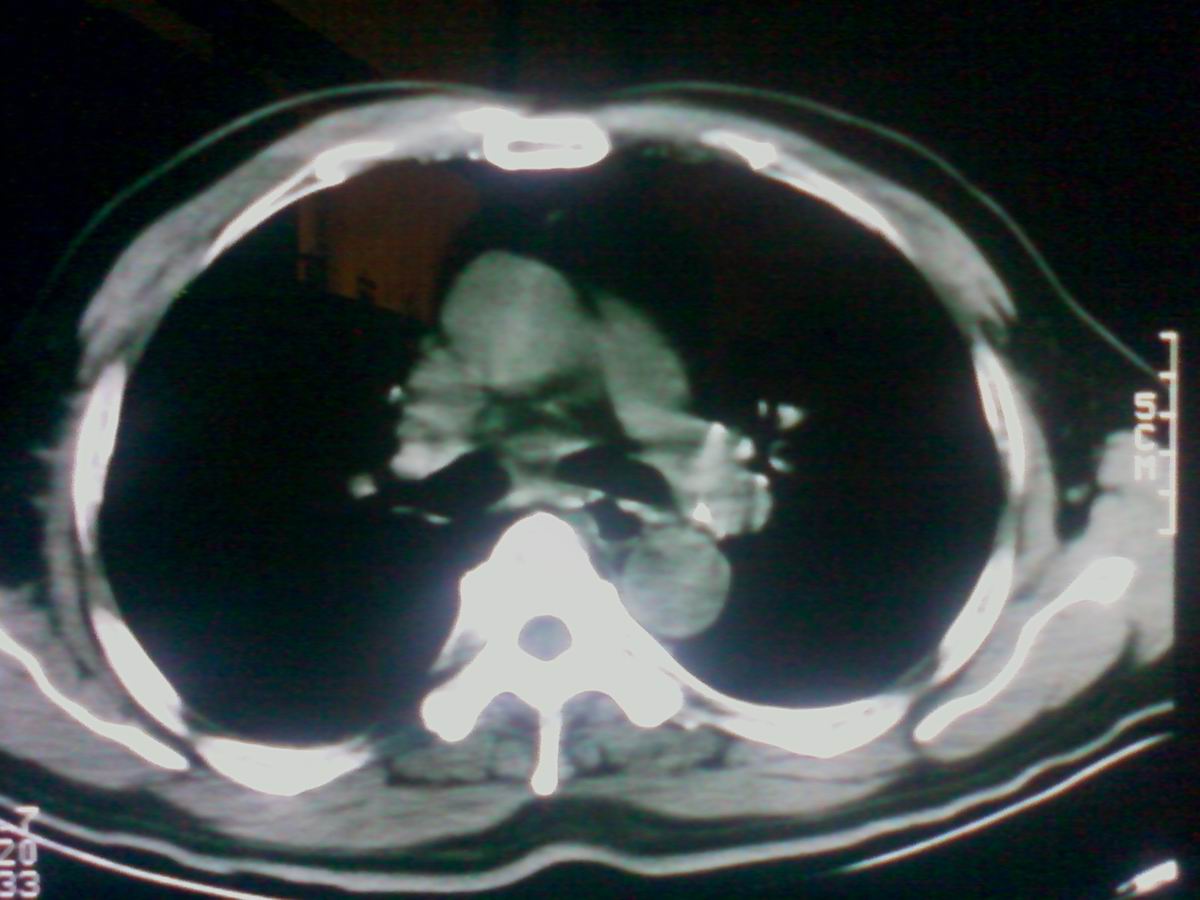

标题: CT25801:患者男性,65岁,临床提示双肺可闻及广泛罗音,看 [打印本页]

标题: CT25801:患者男性,65岁,临床提示双肺可闻及广泛罗音,看

气管后部见半圆形软组织密度病灶,考虑占位,建议气管镜除外鳞癌。

气管上段的肿瘤多为良性乳头状瘤,气管下段的肿瘤多为鳞癌,气管中段的良恶性各占一半。本例位于气管下段,先按恶性处理。不过纤支镜是免不了的。